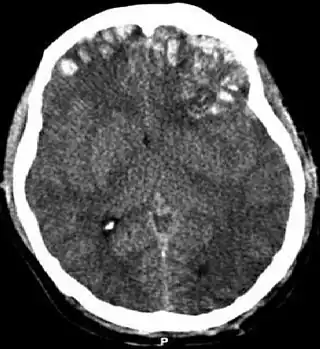

![]() TAC que muestra contusiones cerebrales, hemorragia entre los hemisferios, hematoma subdural en la izquierda y fracturas del cráneo. | ||